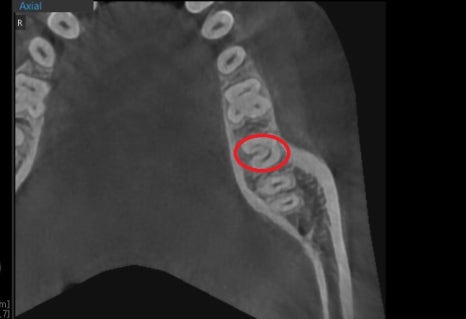

C형 근관이라고 불리는 신경관의 구조는 대표적으로 C1, C2같은 구조와

또 다른 변이된 구조로써 아래와 같이 여러 종류가 있습니다.

위에서 단면을 봤을 때 사진C1과 같이

알파벳 C처럼 신경관 입구가 모두 이어져 있어서

C형 근관은 대부분 하악의 맨 끝 대구치에서 나타나고

이런 치아들은 뿌리가 모아져 있기 때문에

다른 치아들과는 다르게 뿌리끝이 모아져있는 것을 볼 수 있습니다.